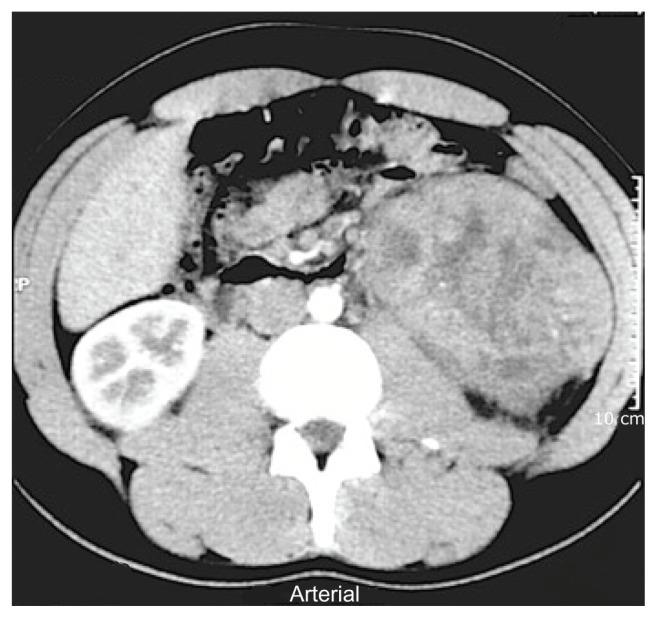

Primary synovial sarcoma (SS) of the kidney is a rare neoplasm and its presenting features are similar to other common renal tumors, making early diagnosis difficult. To date, few cases have been reported in the literature. Primary renal SSs can exist in either a monophasic or a biphasic pattern, the former being more common and tending to have a better prognosis than the biphasic variant. Herein we describe a case of primary renal SS that was diagnosed based on histopathology and immunohistochemistry after radical nephrectomy. Fusion gene product analysis was also done by FISH and RT-PCR. Patient follow-up and literature review are presented, focused on systemic therapy. We highlight that these tumors should be correctly diagnosed as clinical results and specific treatment are distinct from primary epithelial renal cell carcinoma. Adjuvant chemotherapy should be tailored for each patient in the management of disease, although its role still remains unclear.

肾脏原发性滑膜肉瘤(SS)是一种罕见的肿瘤,其表现与其他常见的肾脏肿瘤相似,因此早期诊断较为困难。迄今为止,文献中报道的病例较少。肾脏原发性 SS 可呈现单相或双相模式,前者更为常见,且预后优于双相变体。本文描述了一例经根治性肾切除术后,基于组织病理学和免疫组化诊断为原发性肾脏 SS 的病例。还通过 FISH 和 RT-PCR 进行了融合基因产物分析。本文呈现了患者随访和文献复习的结果,重点介绍了系统治疗。我们强调,这些肿瘤应正确诊断,因为临床结果和特定治疗与原发性上皮性肾细胞癌不同。在疾病管理中,应根据每位患者的情况进行辅助化疗,尽管其作用仍不清楚。